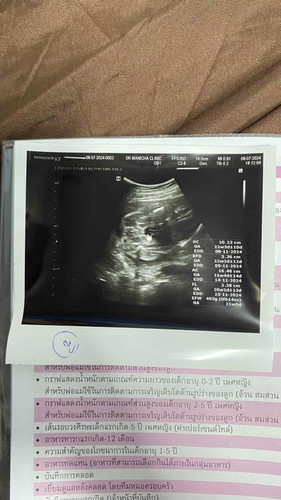

รู้ตัวตอนท้อง5เดือนสามารถตรวจดาวน์ซินโดรมได้มั้ยคะ🥺

ทางคลินิกที่ฝากครรภ์บอกได้แค่ซาวน์ดูแต่ทำไรไม่ได้แล้ว ตอนนี้กังวลมากๆเลยค่ะ แม่แฟนมีลูกเป็นดาวน์ซินโดรมคนนึงเกิดจากครรภ์เป็นพิษ แบบนี้โอกาสเสี่ยงเป็นสูงมั้ยคะ😞